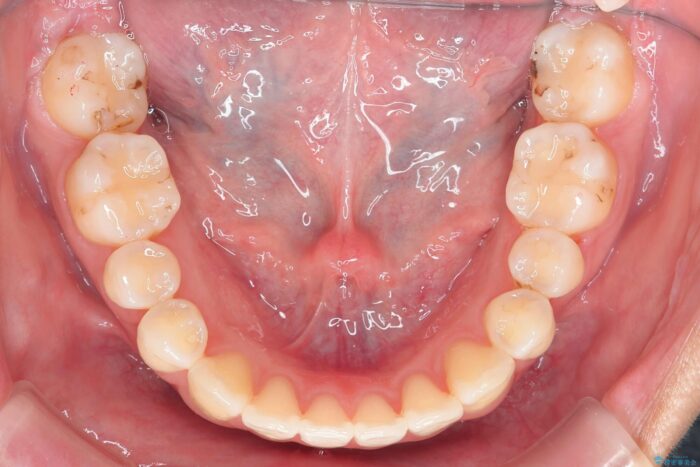

噛まない前歯と捻じれてしまった歯を改善したいと、矯正治療を希望された患者様です。

マルチブラケットを用いた非抜歯のワイヤー矯正で噛み合わせと歯並びを改善していきます。

1年で歯並び、嚙み合わせともにしっかりと改善されました。